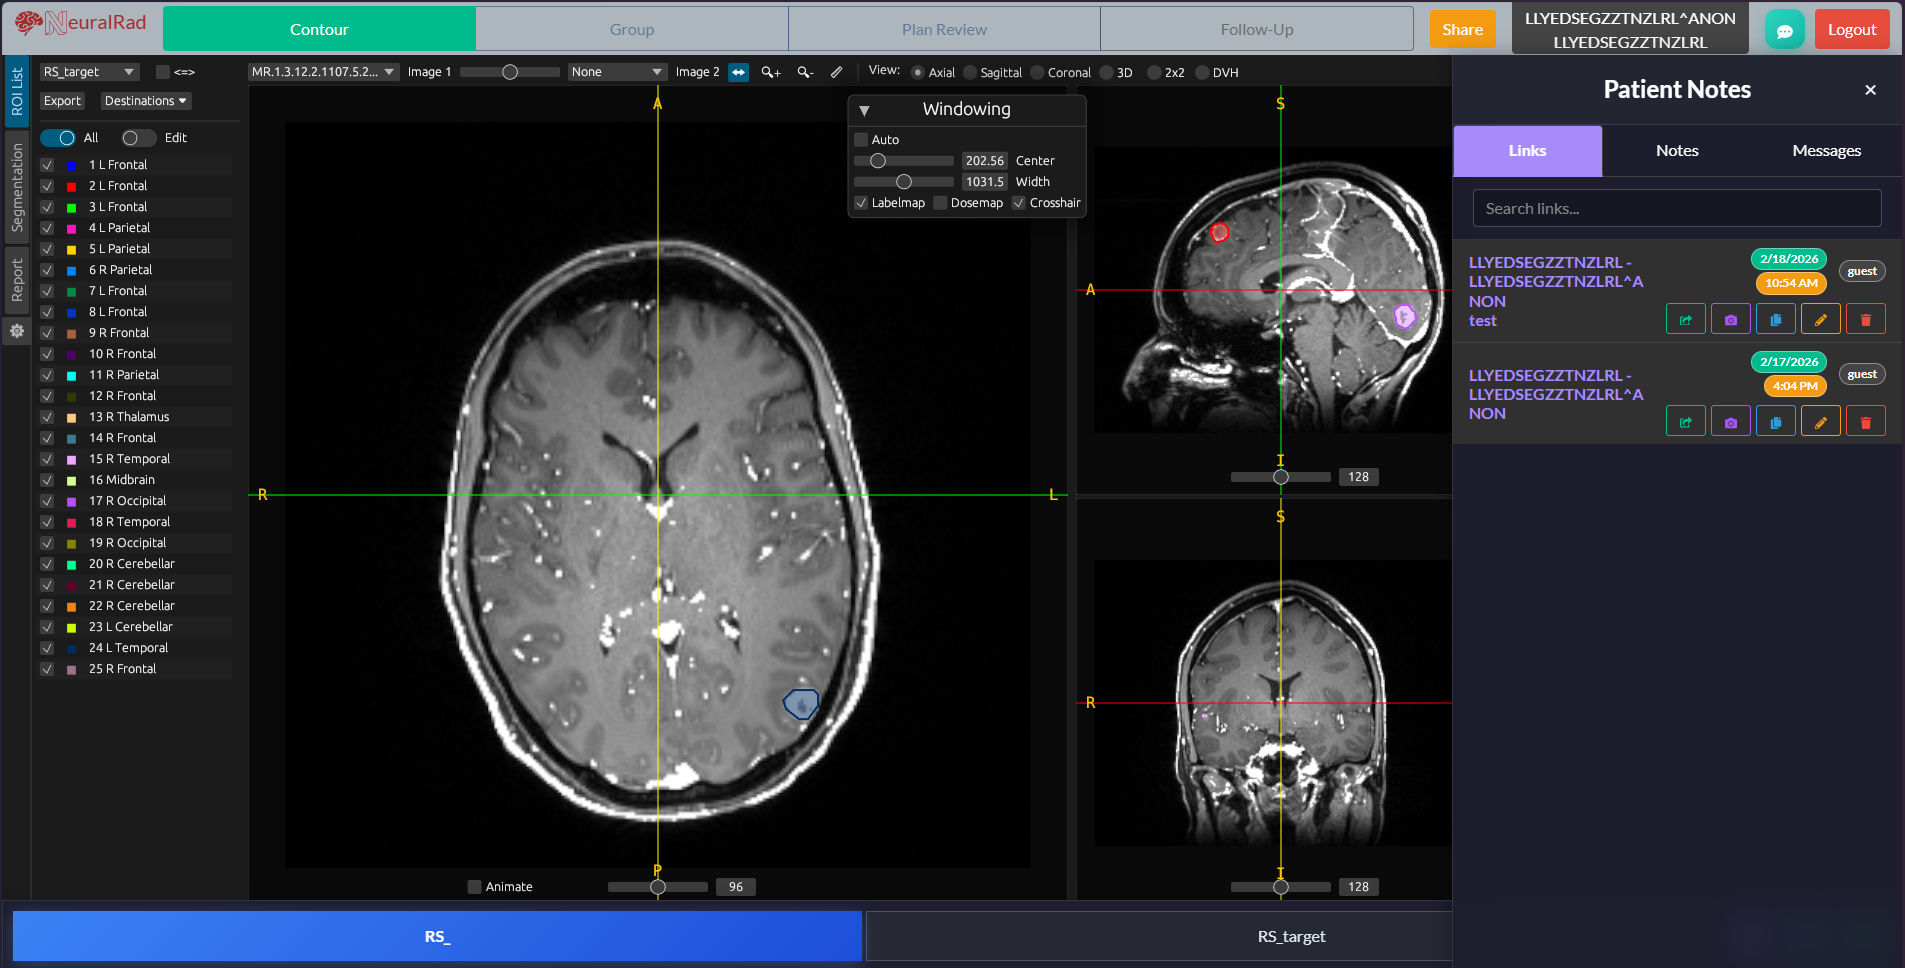

Brain

AI-Powered Stereotactic Radiosurgery Platform

Revolutionizing brain metastasis treatment with automated lesion detection, segmentation, and multi-course tracking. Built for radiation oncologists who demand precision.